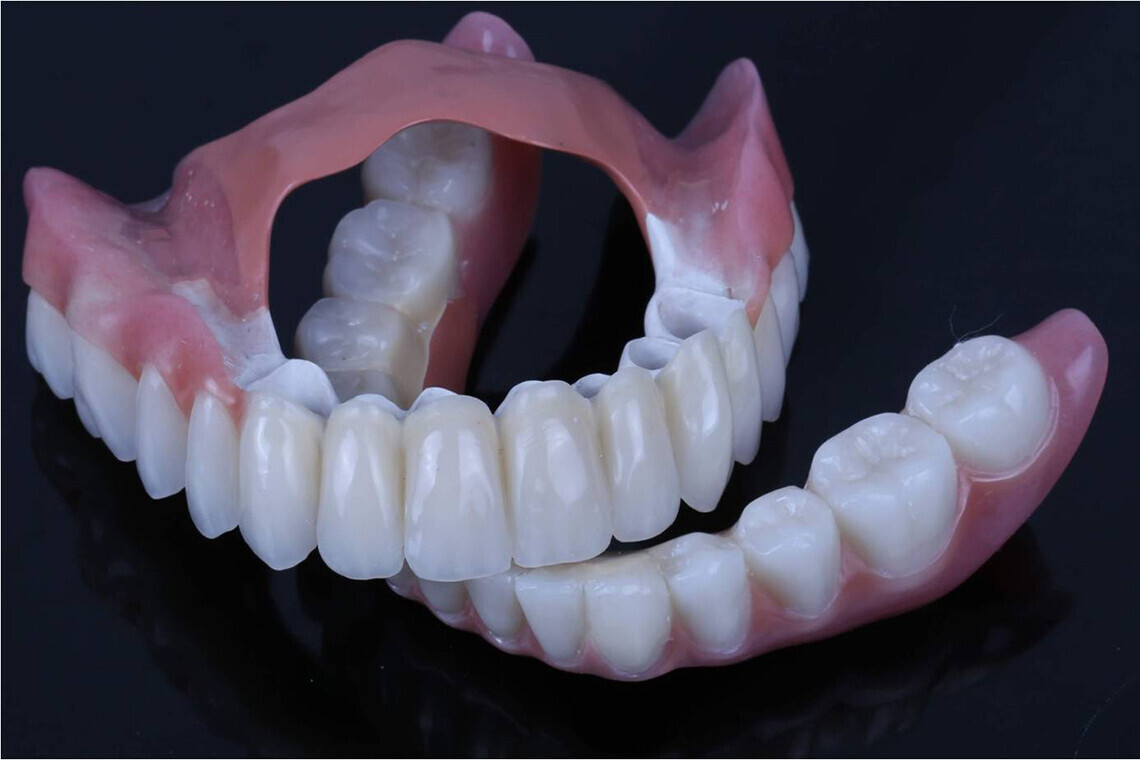

Телескопический бюгельный протез состоит из двух частей: съемной и несъемной. Внутренняя коронка получила название — патрица. Она крепится к зубу. Наружная часть протеза — матрица. Это и есть съемная часть.

Съемная часть:

- Собственно базис.

- Металлический или циркониевый колпачок, который вмонтирован в базис протеза.

Несъемная часть — колпачок, изготовленный из металла или циркония. Он основательно крепится на опорном зубе и имеет вид цилиндра. Основное назначение несъемной части конструкции — фиксация протеза.

Съемная часть — собственно протез. Может быть изготовлен из металла и пластмассы или из BioHPP (инновационный класс материалов, применяемых для изготовления каркасов в протезировании). Протезы из BioHPP легкие и прочные, меньше вызывают раздражение и не оказывают такого давления на слизистую.